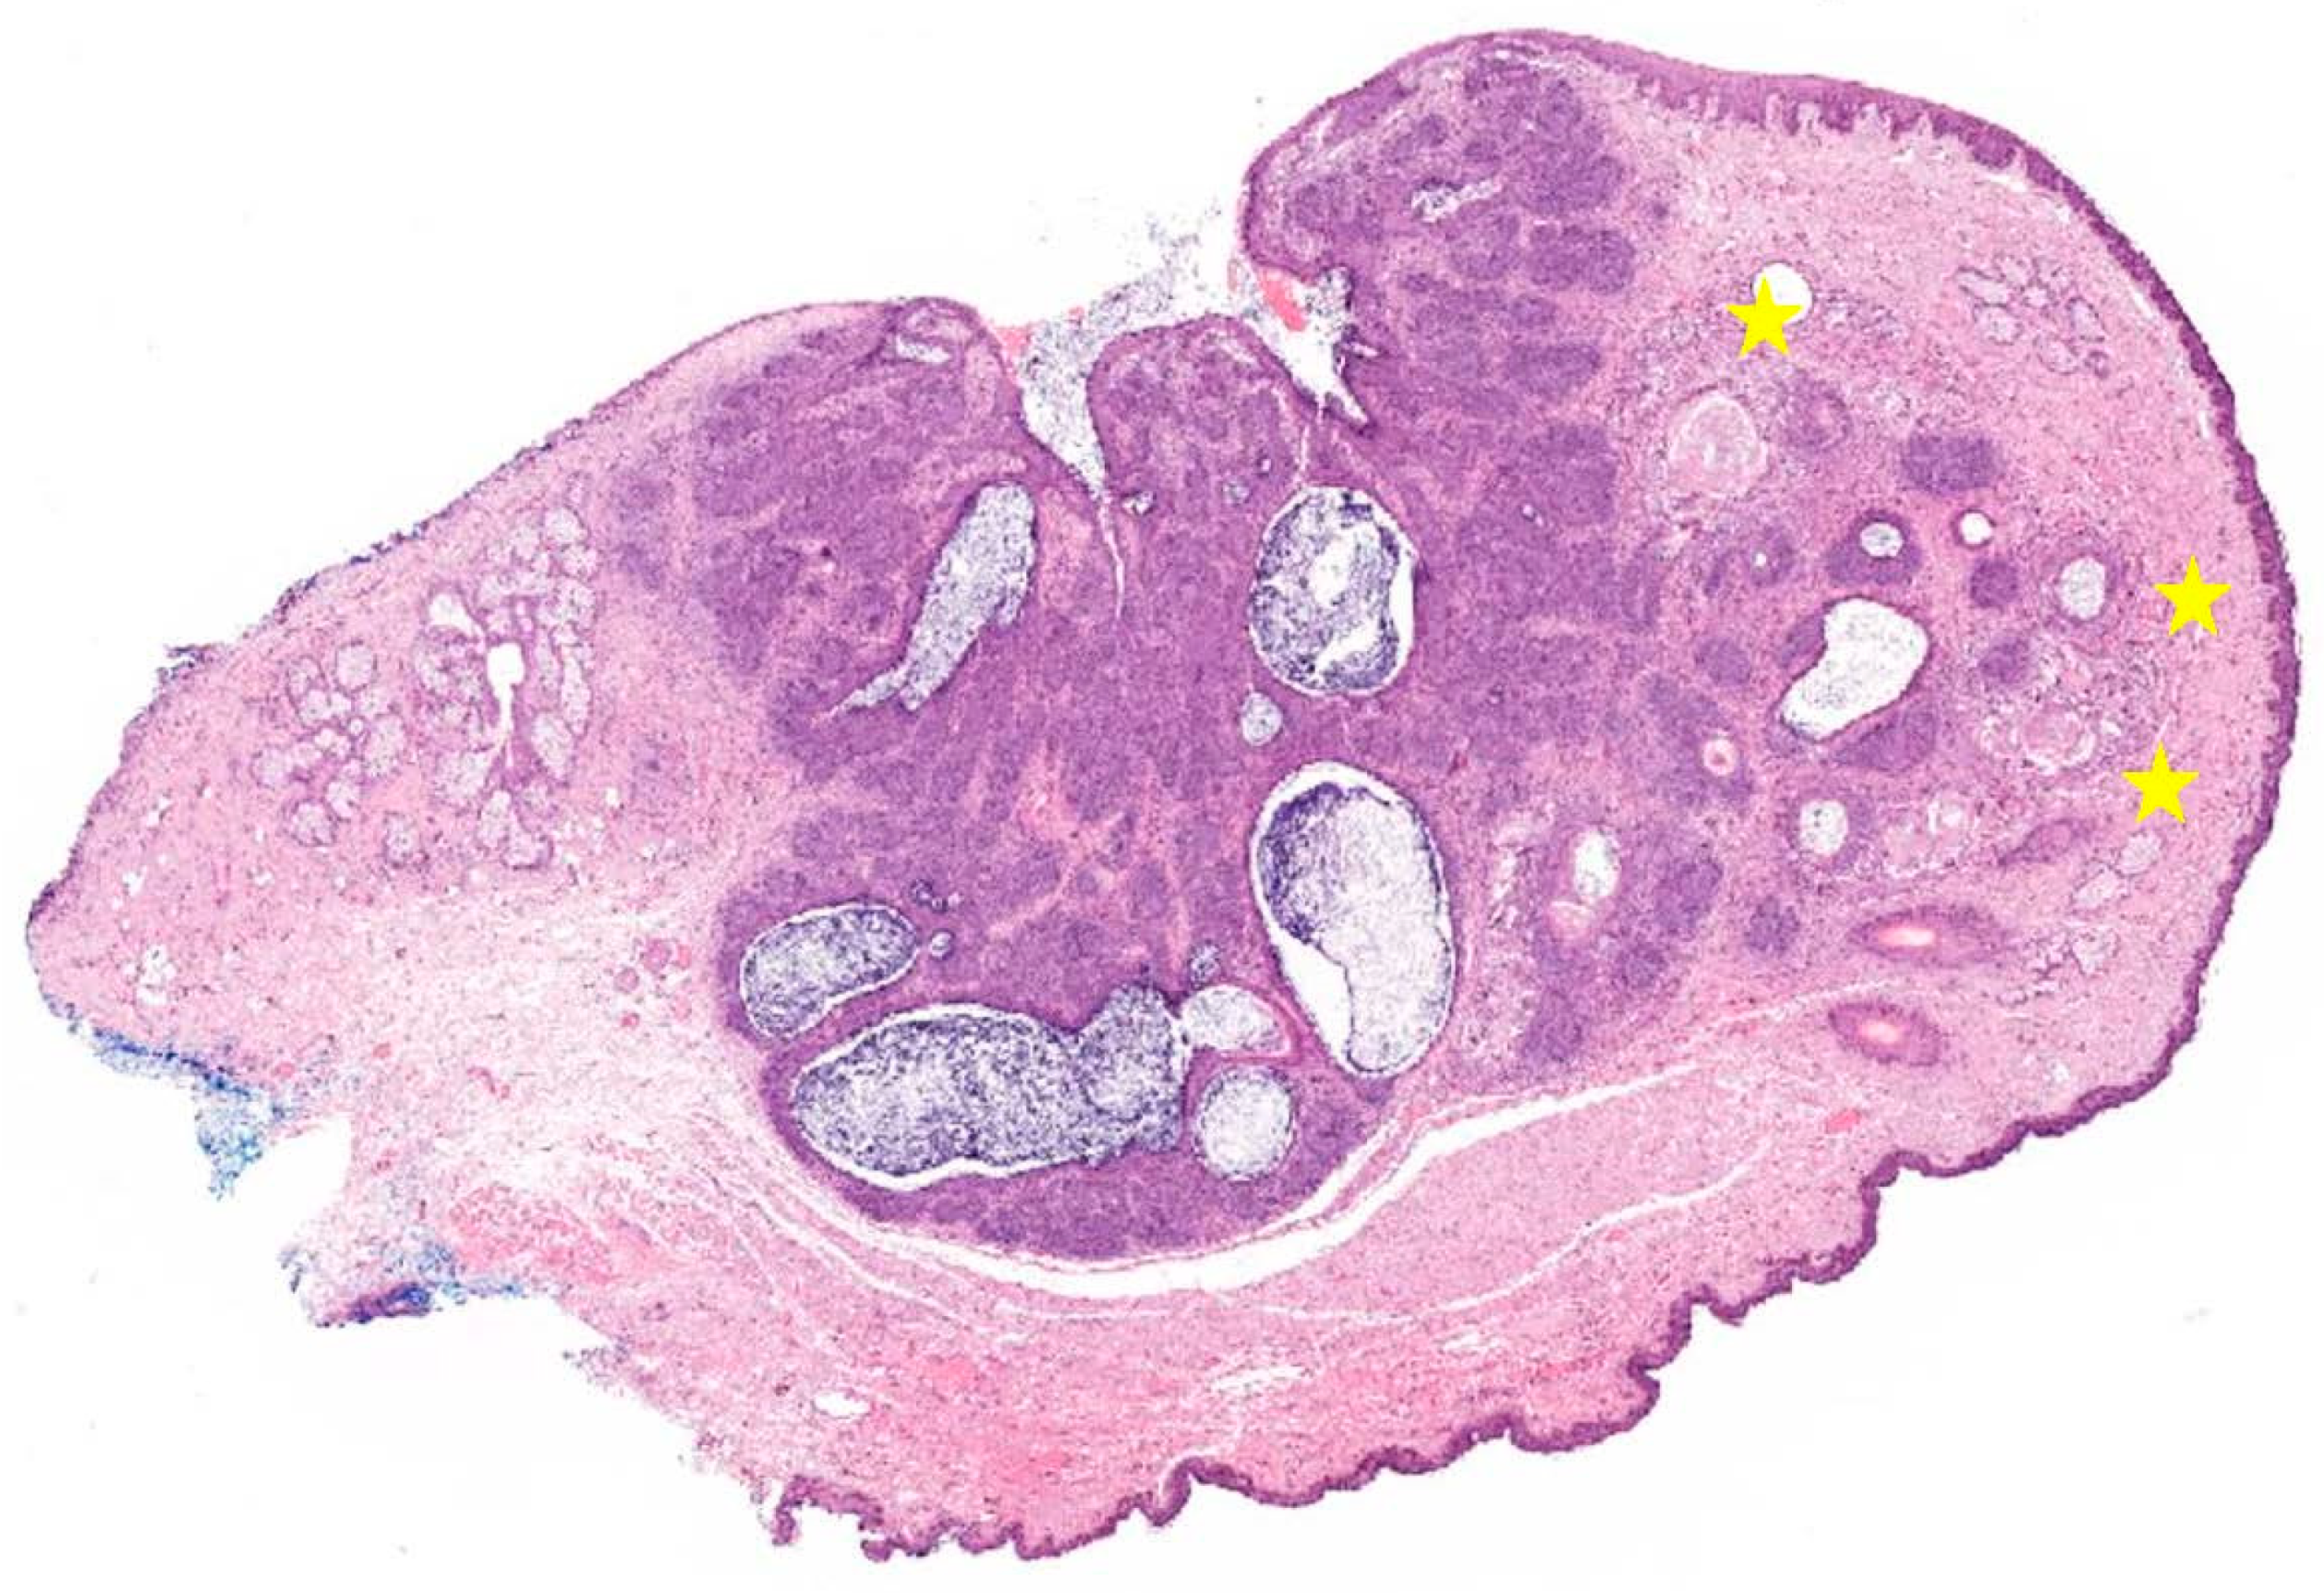

2. Case Presentation